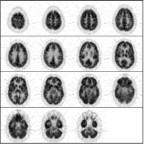

Neurological scans are normally presented with the right/left sides of the brain reversed with respect to the viewer. In an FDG-PET scan metabolism should be symmetrical from side-to-side.

Likewise, metabolism should be similar between the anterior and posterior regions of the brain.